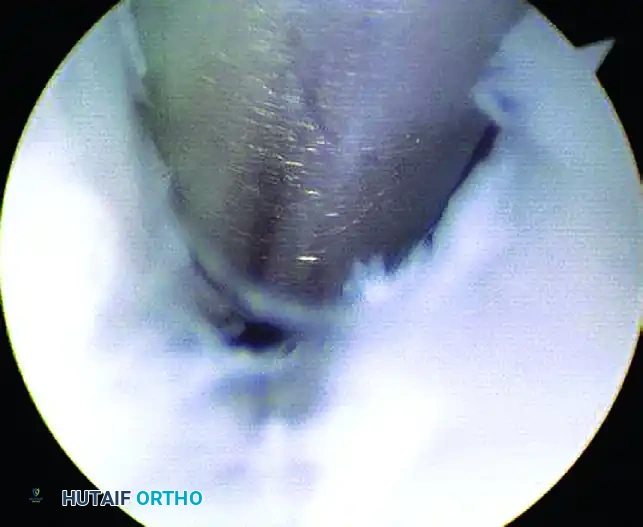

• Lateral Aspect Debridement: Rotate the arthroscope and working instruments to address the lateral aspect of the posterior facet, where the debridement of reactive synovitis and fibrotic tissue is often necessary.

Image

FIGURE 50-15 Arthroscopic view demonstrating the lateral aspect of the posterior facet where débridement of synovitis is often necessary. Switch portals as needed for better access.

Throughout the procedure, the surgeon should frequently switch the arthroscope and the shaver between the central and anterolateral portals to maximize the field of view and ensure comprehensive joint clearance.